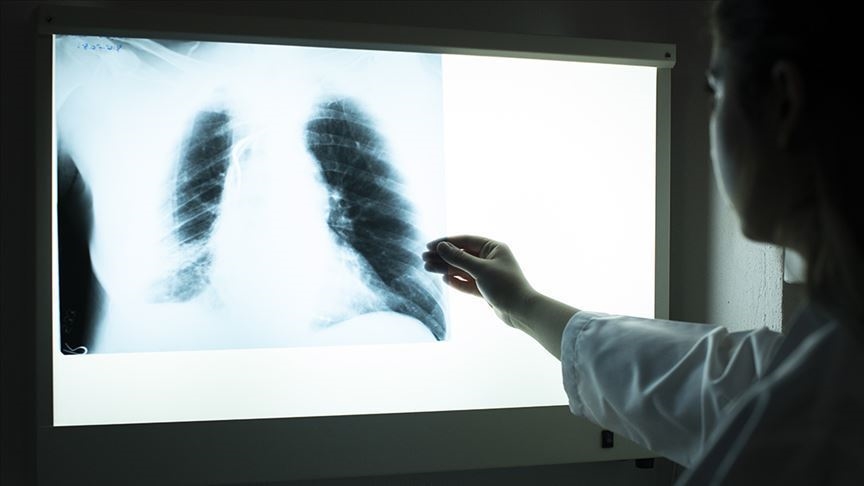

Akciğer kanseri meme kanserinden sonra en sık görülen ve tedavisi zor hastalıklar arasında yer alıyor. Bütün hastalıklarda olduğu gibi akciğer kanserinde de erken teşhis hayat kurtarıyor. Akciğer kanserinin gündelik hayatımızda grip ve nezle gibi hastalıkların belirtileri ile benzerlik gösterdiği için far edilmesi zorlaşıyor. Kronik ve sıklıkla tekrar eden belirtileriniz varsa kontrol için doktora gitmeniz en doğrusu olacaktır. Peki akciğer kanseri nasıl anlaşılır? Belirtileri neler?

Kanser hayatımızın gerçekliği olan hastalıklardan biri. Erken teşhis edildiği takdirde tedavi edilebilen akciğer kanserine karşı dikkatli olmakta fayda var. Genellikle sigara içen ya da sigara dumanına maruz kalan kişilerde görülen akciğer kanserine ilişkin detaylar haberimizde...